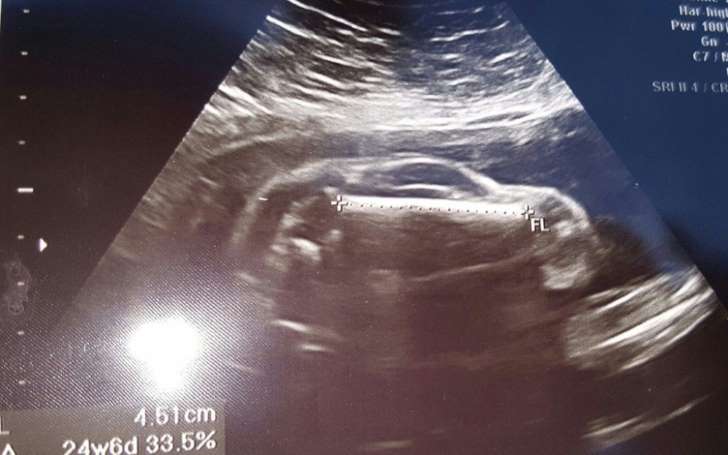

Hình ảnh siêu âm của thai phụ người Anh.

Theo đó, thay vì được thấy mắt, mũi, chân tay của con mình, đôi vợ chồng này chỉ nhận ra các bộ phận của một chiếc xe thể thao như hai bánh xe, mui xe, cửa sổ và thậm chí là một thứ gì đó rất giống vô lăng.Không lâu sau khi được đăng tải, bức ảnh này gây bão, càn quét trên hầu khắp các trang mạng xã hội và trở thành chủ đề tranh cãi của nhiều người về lý do tại sao đứa trẻ lại có hình dạng như vậy.